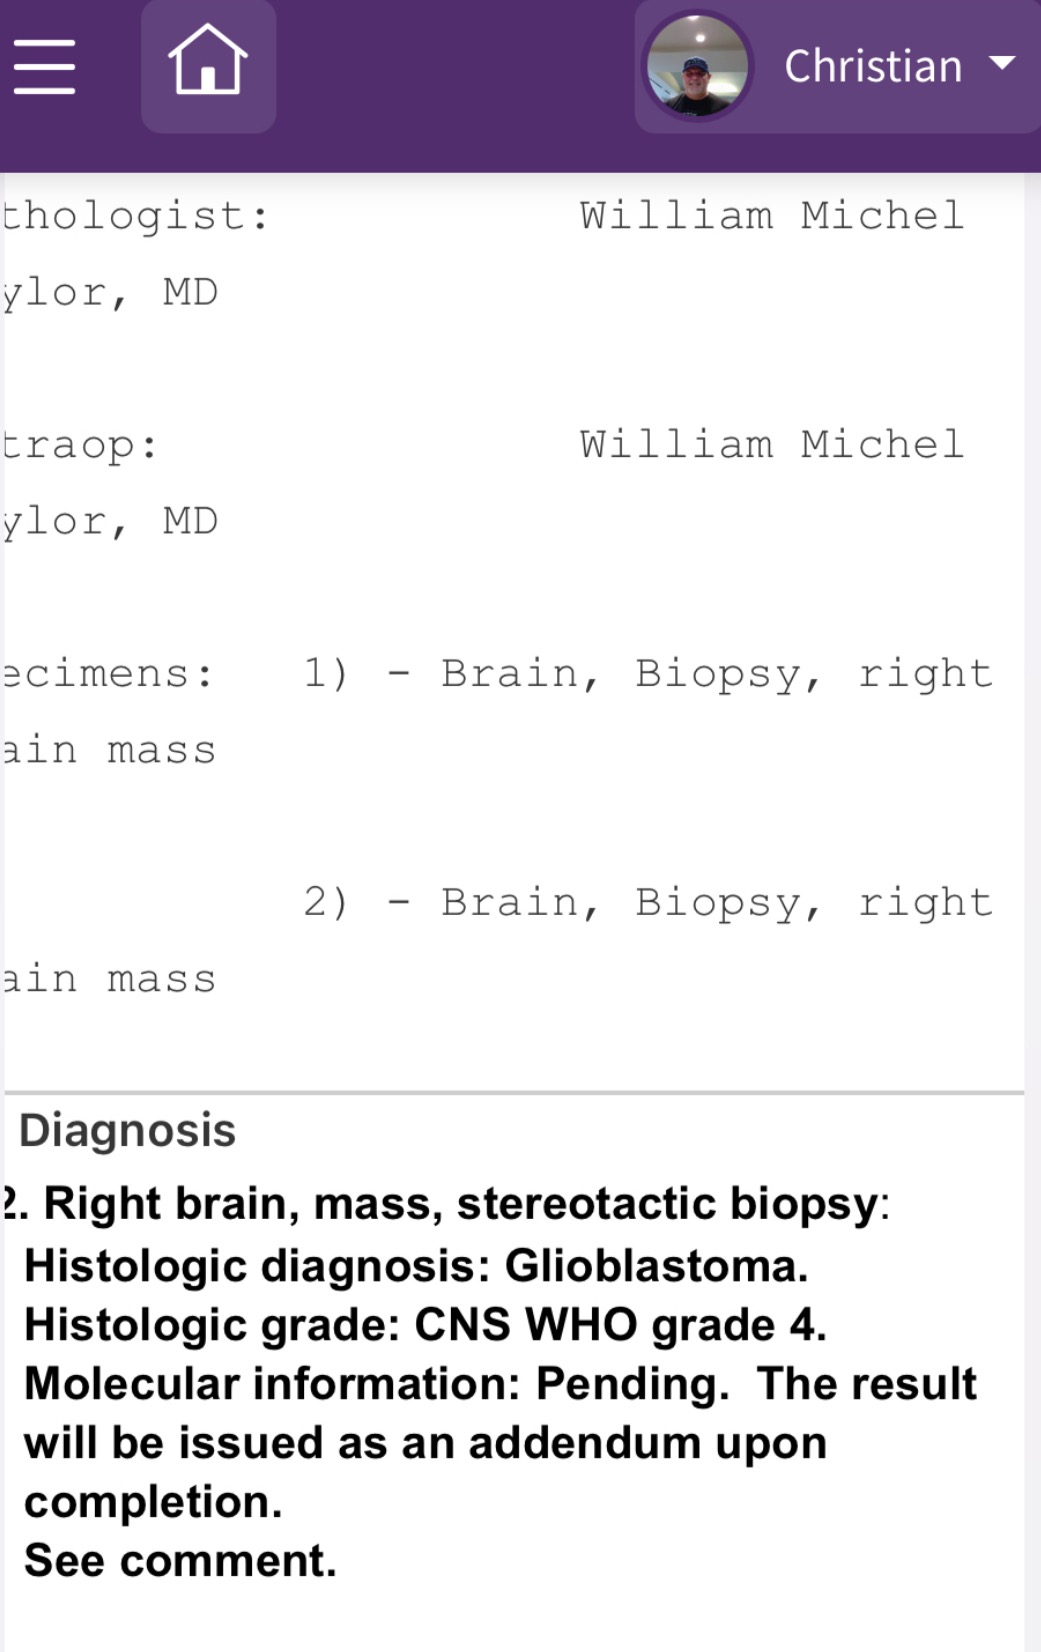

In April of 2025, Christian began experiencing seizures. Over the following months, things escalated: he's now had over 200 seizures and two strokes, leading to multiple physical injuries. On July 8th, 2025, Christian was diagnosed with Stage 4 Glioblastoma (GBM)—a rare, highly aggressive brain cancer that affects just 1% of men his age.

His first major brain surgery is Thursday, July 17th, 2025. Doctors have given him a prognosis of just 9-14 months, *if* he survives the surgery and endures a difficult course of chemo and radiation. His medical bills have already surpassed $400,000, and the financial burden is overwhelming.